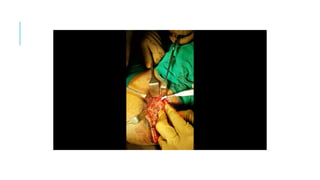

THE COURSE OF TREATMENT

Embolization of pelvic AVM done

>95% flow reduction achieved

Plan for excision of AVM in right

gluteal region done under general

anaesthesia after taking high risk

consent and consent for colostomy

THE COURSE OFTREATMENT Embolization of pelvic AVM done >95% flow reduction achieved Plan for excision of AVM in right gluteal region done under general anaesthesia after taking high risk consent and consent for colostomy